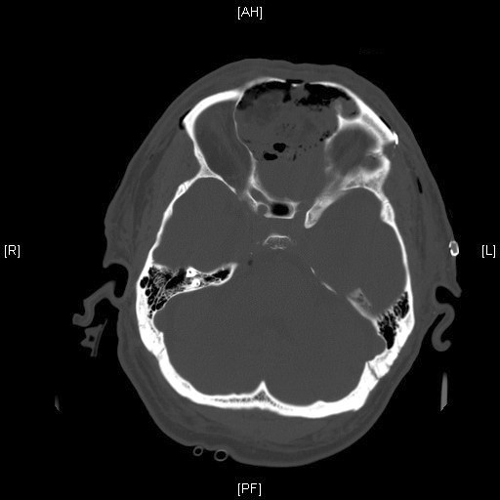

Radiologic Images of the Case: CT scan demonstrated a large midline mixed density mass with fat density that occupies the ethmoid sinus with extension through the cribiform plate into the inferior portion of the anterior cranial fossa. The mass is 5.1 x 3.2 cm in greatest dimension (Panel A). Bone windows of CT scan demonstrated bone expansion suggestive of remodeling (Panel B). On MRI, spoiled gradient recalled (SPGR ) post contrast images showing mass is either avidly enhancing or bright on T1 precontrast. (Panel C). The mass hypointense signal intensity compared to brain parenchyma with surrounding areas of increased signal (suggestive of entrapped mucus) on T2 weighted images (Panel D and E).